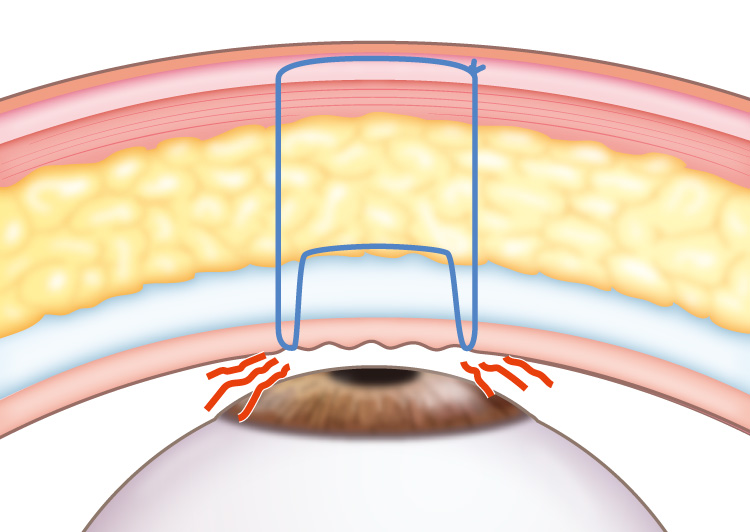

主に上まぶたの眼瞼挙筋を短縮させて縫合していき修正を行っていきます。

まぶたを開けるための筋肉である上まぶたの眼瞼挙筋(がんけんきょきん)の短縮量を調整して縫合する修正手術を行うことが可能です。

このとき、同時に一重から二重にすることも可能です。

目の開きに左右差がある場合も片方か、両方を手術して、バランスがとれるように調整していきます。

眼瞼挙筋を過度に短縮したことによって、目が開きすぎていると考えられます。

短縮しすぎた眼瞼挙筋をゆるめて再調整することによって、ちょうどいい目の開き具合に修正できることが多いです。